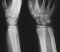

Angiogram of the wrist and hand Reflect the origin of adductor pollicis. Dissect dorsal and palmar interosseous muscles; determine position, structure, dual insertion, and action. Observe these muscles on both the palmar and dorsal sides of the hand. Follow these muscles to their insertions on proximal phalanges and extensor expansions.

Consider the complete blood supply to the hand: sources, arches (how many and how formed?). How do the dorsal and palmar proper digital arteries differ in their formation? What are perforating arteries? Where are they found? Function?

Growth plates at the wrist Colles' fracture